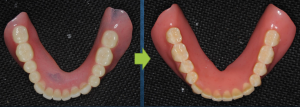

残っている歯が数本あって、それらを抜いて総入れ歯にする場合には治療用義歯に粘膜調整材という白い軟性の材料を使って理想的な形を追求していくことが多いです。この作業は結構奥が深くて、術者の経験やイメージに左右されます。どういう形がその患者さんにとって最も口の中で安定し快適なのか。無から有を作り出す総義歯医療はやりがいもある反面、困難なケースにも対応できるように常に勉強、準備が必要と思います。勉強と言っても本や単発の講習会参加だけでは私の場合には十分でないように思います。以前から参加し続けている咬合セミナー、勉強会のメンバーは1日中総義歯だけでお互いのケースを提示しながら活発な討論ができるので非常に助かっています。総義歯医療については、たとえ患者さんが満足したとしても、もっとこうすればよかったのではないか、もっとうまくなりたい、などという思いは尽きることがありません。

理想的な形を追求(東京大手町勤務歯科医の総義歯、全顎治療ブログ)